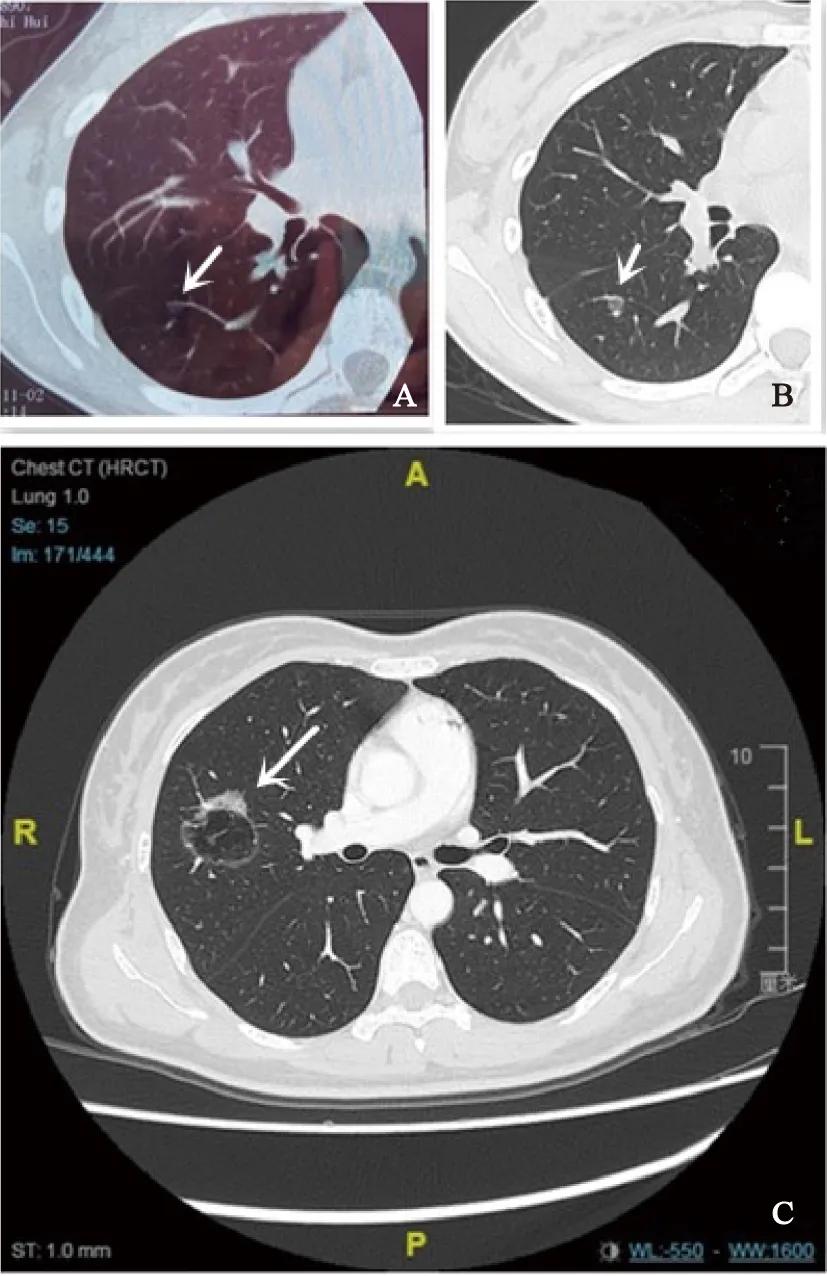

第1例患者是1例14岁女孩,由于持续发热和咳嗽而于2018年5月11日在患者所在地医院进行胸部CT检查,结果显示,右下背部肺段有一个6 mm的磨玻璃样结节(图1A)。观察1年后(2019年5月31日),结节仍然存在并且比以前大2 mm(图1B)。经过3个月的进一步观察,结节无明显变化。后在2019年8月进行胸腔镜亚肺叶切除术,术后病理学诊断为微浸润性腺癌。若不是偶然地一次胸部CT检查,那么这个磨玻璃样结节在10年后会给这个小女孩带来什么样的后果?20年后又会怎么样?

另1例是38岁、3 cm混杂磨玻璃样结节的女性(图1C),接受了胸腔镜下右上肺叶切除加纵隔淋巴结清扫术。术后病理学检查结果显示为腺癌,但第12组(1/9)淋巴结转移,TNM分期为T2aN1M0(ⅡB分期)。如果她在5~10年前接受过肺癌筛查并进行了浸润前的手术,预后将截然不同。

图 1 1例14岁和l例38岁患者胸部CT影像